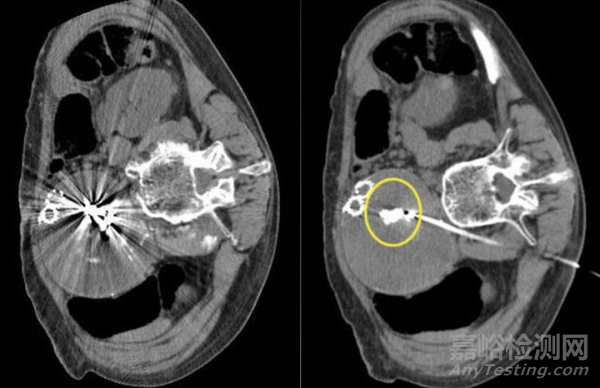

首先是影像偽影問題。金屬材質(zhì)在CT或MRI影像下,往往造成密度過高的白色斑塊遮蔽周圍組織。臨床數(shù)據(jù)顯示,金屬線圈在CT/MRI檢查中可導(dǎo)致30-50%的血管區(qū)域出現(xiàn)偽影。這直接影響醫(yī)生術(shù)后判斷病變是否完全閉塞,或者是否存在并發(fā)癥,尤其在腫瘤復(fù)發(fā)監(jiān)測等精細(xì)場景中更顯突出。

更重要的是,NED聚合物在顯影原理上同樣具備創(chuàng)新。Embolization通過在聚合物結(jié)構(gòu)中引入碘化造影劑,實(shí)現(xiàn)了X線透視下的可視性。但與金屬不同,這種顯影方式不會在CT或MRI產(chǎn)生強(qiáng)烈偽影。動(dòng)物實(shí)驗(yàn)數(shù)據(jù)顯示,NED相較于傳統(tǒng)鉑金或鎳鈦線圈,影像偽影減少幅度可達(dá)70%。對于需要術(shù)后影像隨訪的患者群體而言,這意味著術(shù)后CT或MRI能更清晰地呈現(xiàn)病變閉塞狀態(tài),減少不必要的二次檢查。